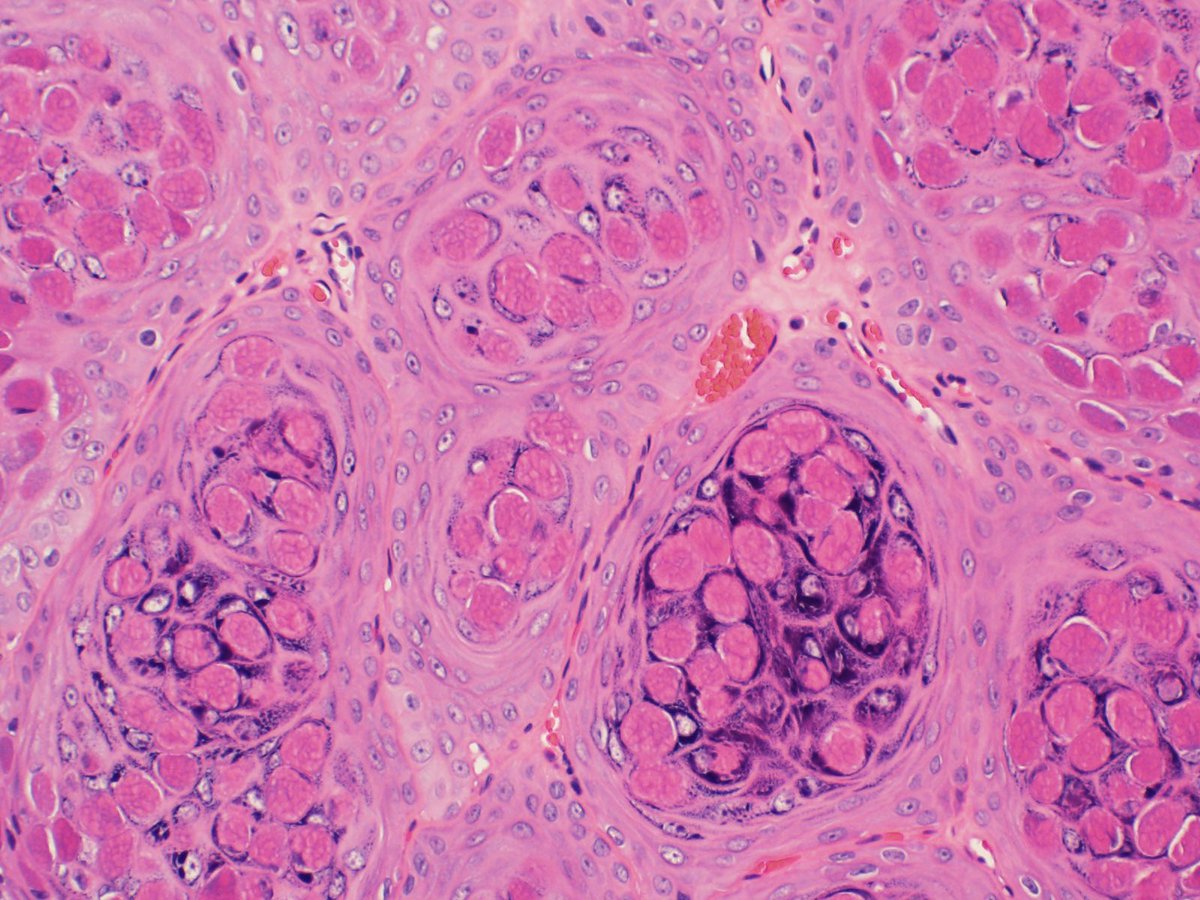

#ThrowbackThursday to a couple weeks ago. This time it’s vulvar biopsy of a lesion from a young female in her 20’s, on chronic immunosupression for a kidney transplant. What is the infectious agent? #dermpath #gynpath #pathology #microbiology